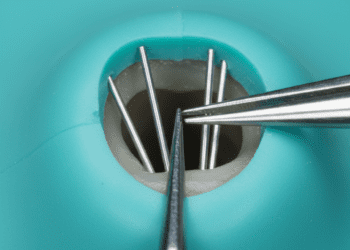

Raízes dentárias

As raízes podem variar em número e formato dependendo do tipo de dente e da arcada (maxilar ou mandibular). Em geral:

- Incisivos e caninos normalmente possuem uma única raiz cônica.

- Pré-molares podem ter uma ou duas raízes, dependendo do dente e da arcada.

- Molares geralmente apresentam múltiplas raízes, que podem variar de duas a três raízes, a fim de oferecer maior estabilidade.

As raízes são revestidas externamente pelo cemento e se conectam ao osso alveolar pelo ligamento periodontal, formando a base estrutural que mantém o dente fixo na boca.